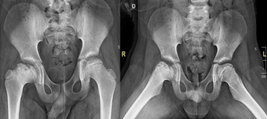

Preoperative planning is carried out through imaging studies, digital segmentation and 3D printing of the right hip (Figure 4), where the CAM-type morphology lesion can be evidenced. In the programmed operative room, under general anesthesia, in left lateral decubitus, an anterior approach to the hip is performed and dissection by planes up to the fascia, which is excised. Subsequently, an osteotomy of the greater trochanter is performed, release of the gluteus medius, the joint capsule is released, observing the femoral head with healthy articular cartilage; capsulotomy is performed and the Impingement test is performed under direct vision. Then, controlled hip dislocation is performed using a flexion and adduction maneuver, and resection of the anterolateral portion of the coxa magna is performed with an osteotome and shaver (DePuy-Synthes). Finally, hip reduction is performed and compliance is visualized under fluoroscopic vision in two planes, the greater trochanter is transposed and fixed with 2 6.5 mm cannulated screws (DePuy-Synthes), reduction compliance is visualized with fluoroscopic vision, and it is verified with direct visualization with a 3D model, suture is performed and the post-surgical cleaning with sterile dressings and gauze is performed, ending the procedure without complications. Radiological control is performed (Figure 5) and due to satisfactory postoperative evolution, medical discharge is decided after 24 hours. Radiographic control is performed at 6 months, where appropriate bone healing is evidenced (Figure 6).

Figure 5 AP Pelvis X-ray for 24 hrs post op.

Figure 6 6 months follow up Pelvis X-ray.